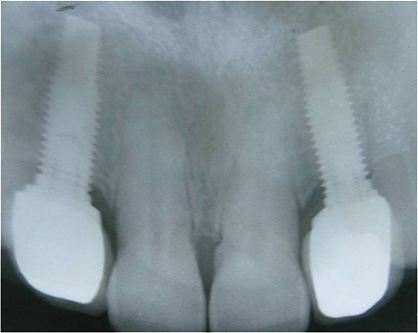

Caso 1 - Implante imediato após extração do dente fraturado (dente 11) e implante imediato

![]() |